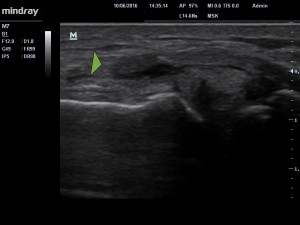

image 1. Kyste méniscal (petite « boule noire » collée au ménisque interne ).

L’examen échographique (image 1 ) retrouve la présence d’un ménisque très hétérogène « bombant » au delà de ses limites normales, mais également d’une  « boule ‘noire’ » collée au ménisque, qui correspond à un kyste méniscal.  L’ensemble est contenu par un ligament (Medial collateral ligament) qui apparait distendu.  Ce kyste, contient une sorte de substance épaissie « mucoïde » et est en rapport avec la dégénérescence du ménisque.

C’est ce kyste qui correspond à la petite induration douloureuse que ressent le patient.